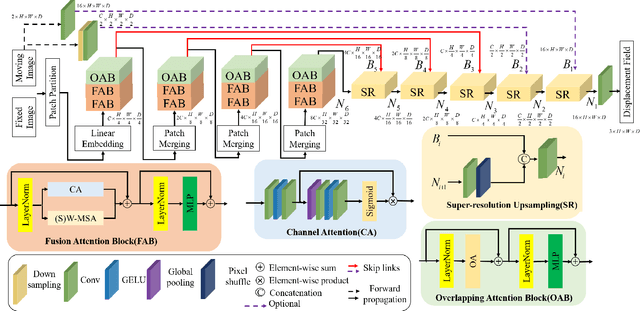

Abstract:Complicated image registration is a key issue in medical image analysis, and deep learning-based methods have achieved better results than traditional methods. The methods include ConvNet-based and Transformer-based methods. Although ConvNets can effectively utilize local information to reduce redundancy via small neighborhood convolution, the limited receptive field results in the inability to capture global dependencies. Transformers can establish long-distance dependencies via a self-attention mechanism; however, the intense calculation of the relationships among all tokens leads to high redundancy. We propose a novel unsupervised image registration method named the unified Transformer and superresolution (UTSRMorph) network, which can enhance feature representation learning in the encoder and generate detailed displacement fields in the decoder to overcome these problems. We first propose a fusion attention block to integrate the advantages of ConvNets and Transformers, which inserts a ConvNet-based channel attention module into a multihead self-attention module. The overlapping attention block, a novel cross-attention method, uses overlapping windows to obtain abundant correlations with match information of a pair of images. Then, the blocks are flexibly stacked into a new powerful encoder. The decoder generation process of a high-resolution deformation displacement field from low-resolution features is considered as a superresolution process. Specifically, the superresolution module was employed to replace interpolation upsampling, which can overcome feature degradation. UTSRMorph was compared to state-of-the-art registration methods in the 3D brain MR (OASIS, IXI) and MR-CT datasets. The qualitative and quantitative results indicate that UTSRMorph achieves relatively better performance. The code and datasets are publicly available at https://github.com/Runshi-Zhang/UTSRMorph.